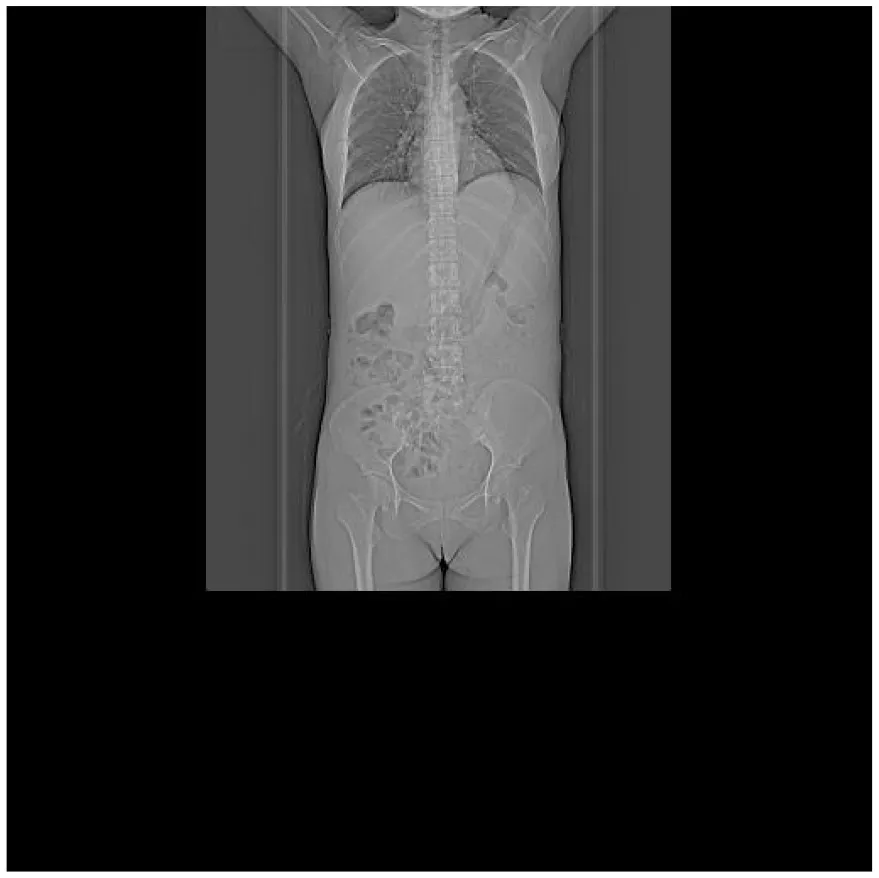

(II) PET/CT: ① Multiple enlarged lymph nodes (bilateral neck I–V, axillae, hila, mediastinum, abdomen, retroperitoneum, and iliac vessels) with mildly increased fluorodeoxyglucose (FDG) uptake and variable C-X-C chemokine receptor type 4 (CXCR4) expression; ② Splenomegaly with diffuse CXCR4 expression, normal FDG uptake; ③ Diffusely increased FDG uptake and CXCR4 expression in bones, suggesting hypercellular marrow; ④ Peritonitis, scattered ascites; ⑤ Subcutaneous edema in neck/chest/abdomen/pelvis/bilateral thighs/buttocks.

| Thorax CT | Multiple enlarged lymph nodes were found in the right heart diaphragmatic angle, intra-abdomen, and retroperitoneum, which were larger than the anterior part; bone density was increased in the sternum, some vertebrae and pelvis, and bilateral femur; a small amount of fluid was found in both pleural cavities, and scattered inflammation was detected in both lungs | |

| Abdomen CT | Multiple enlarged lymph nodes were found in the right heart diaphragmatic angle, intra-abdomen, and retroperitoneum, which were larger than the anterior part; bone density was increased in the sternum, some vertebrae and pelvis, and bilateral femur; a small amount of fluid was found in both pleural cavities, and scattered inflammation was detected in both lungs. Multiple enlarged lymph nodes were found in the right heart diaphragmatic angle, intra-abdomen, and retroperitoneum, which were larger than the anterior part; bone density was increased in the sternum, some vertebrae and pelvis, and bilateral femur; a small amount of fluid was found in both pleural cavities, and scattered inflammation was detected in both lungs | |

CT images of the patient's abdomen.

A and B are abdominal CT scan images before and after autologous stem cell transplantation. A shows a significant amount of ascites, while B indicates a marked reduction in ascites. C, D, and E are PET/CT images before autologous stem cell transplantation, which show increased bone density in multiple areas, elevated FDG metabolism, no abnormal increase in CXCR4 expression; splenomegaly with diffusely increased CXCR4 expression and no abnormal FDG metabolism; and inflammatory changes in the peritoneum with scattered effusions in the abdomen and pelvis. F shows improvement after treatment.